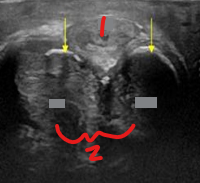

What is the sonographic appearance of benign prostatic hypertrophy (BPH)?

Diffuse prostatic enlargement with volume > 30 mL

Punctate calcifications or corpora amylacea

Nodule and cystic formation

Hypervascular inner gland